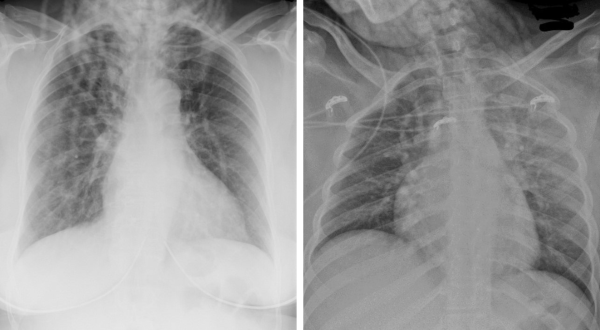

(Left) How large twists appear on a chest x-ray; (right) how small braids, starting with cornrows on the scalp, present on a chest x-ray.

That’s why their research is focused on educating radiologists—and Emergency Department physicians, too—about how Black hairstyles appear on scans. “We started by identifying the five popular Black hairstyles: small braids, large braids, small twists, large twists, and locs,” Udongwo says.

She and Dr. Maresky then created a board with examples of each style, and prepared slides to show what they look like on different types of imaging. “We wanted to be able to tell radiologists, ‘This is how a certain style appears on a radiograph, a chest x-ray, and a CT slice,’” Udongwo explains.